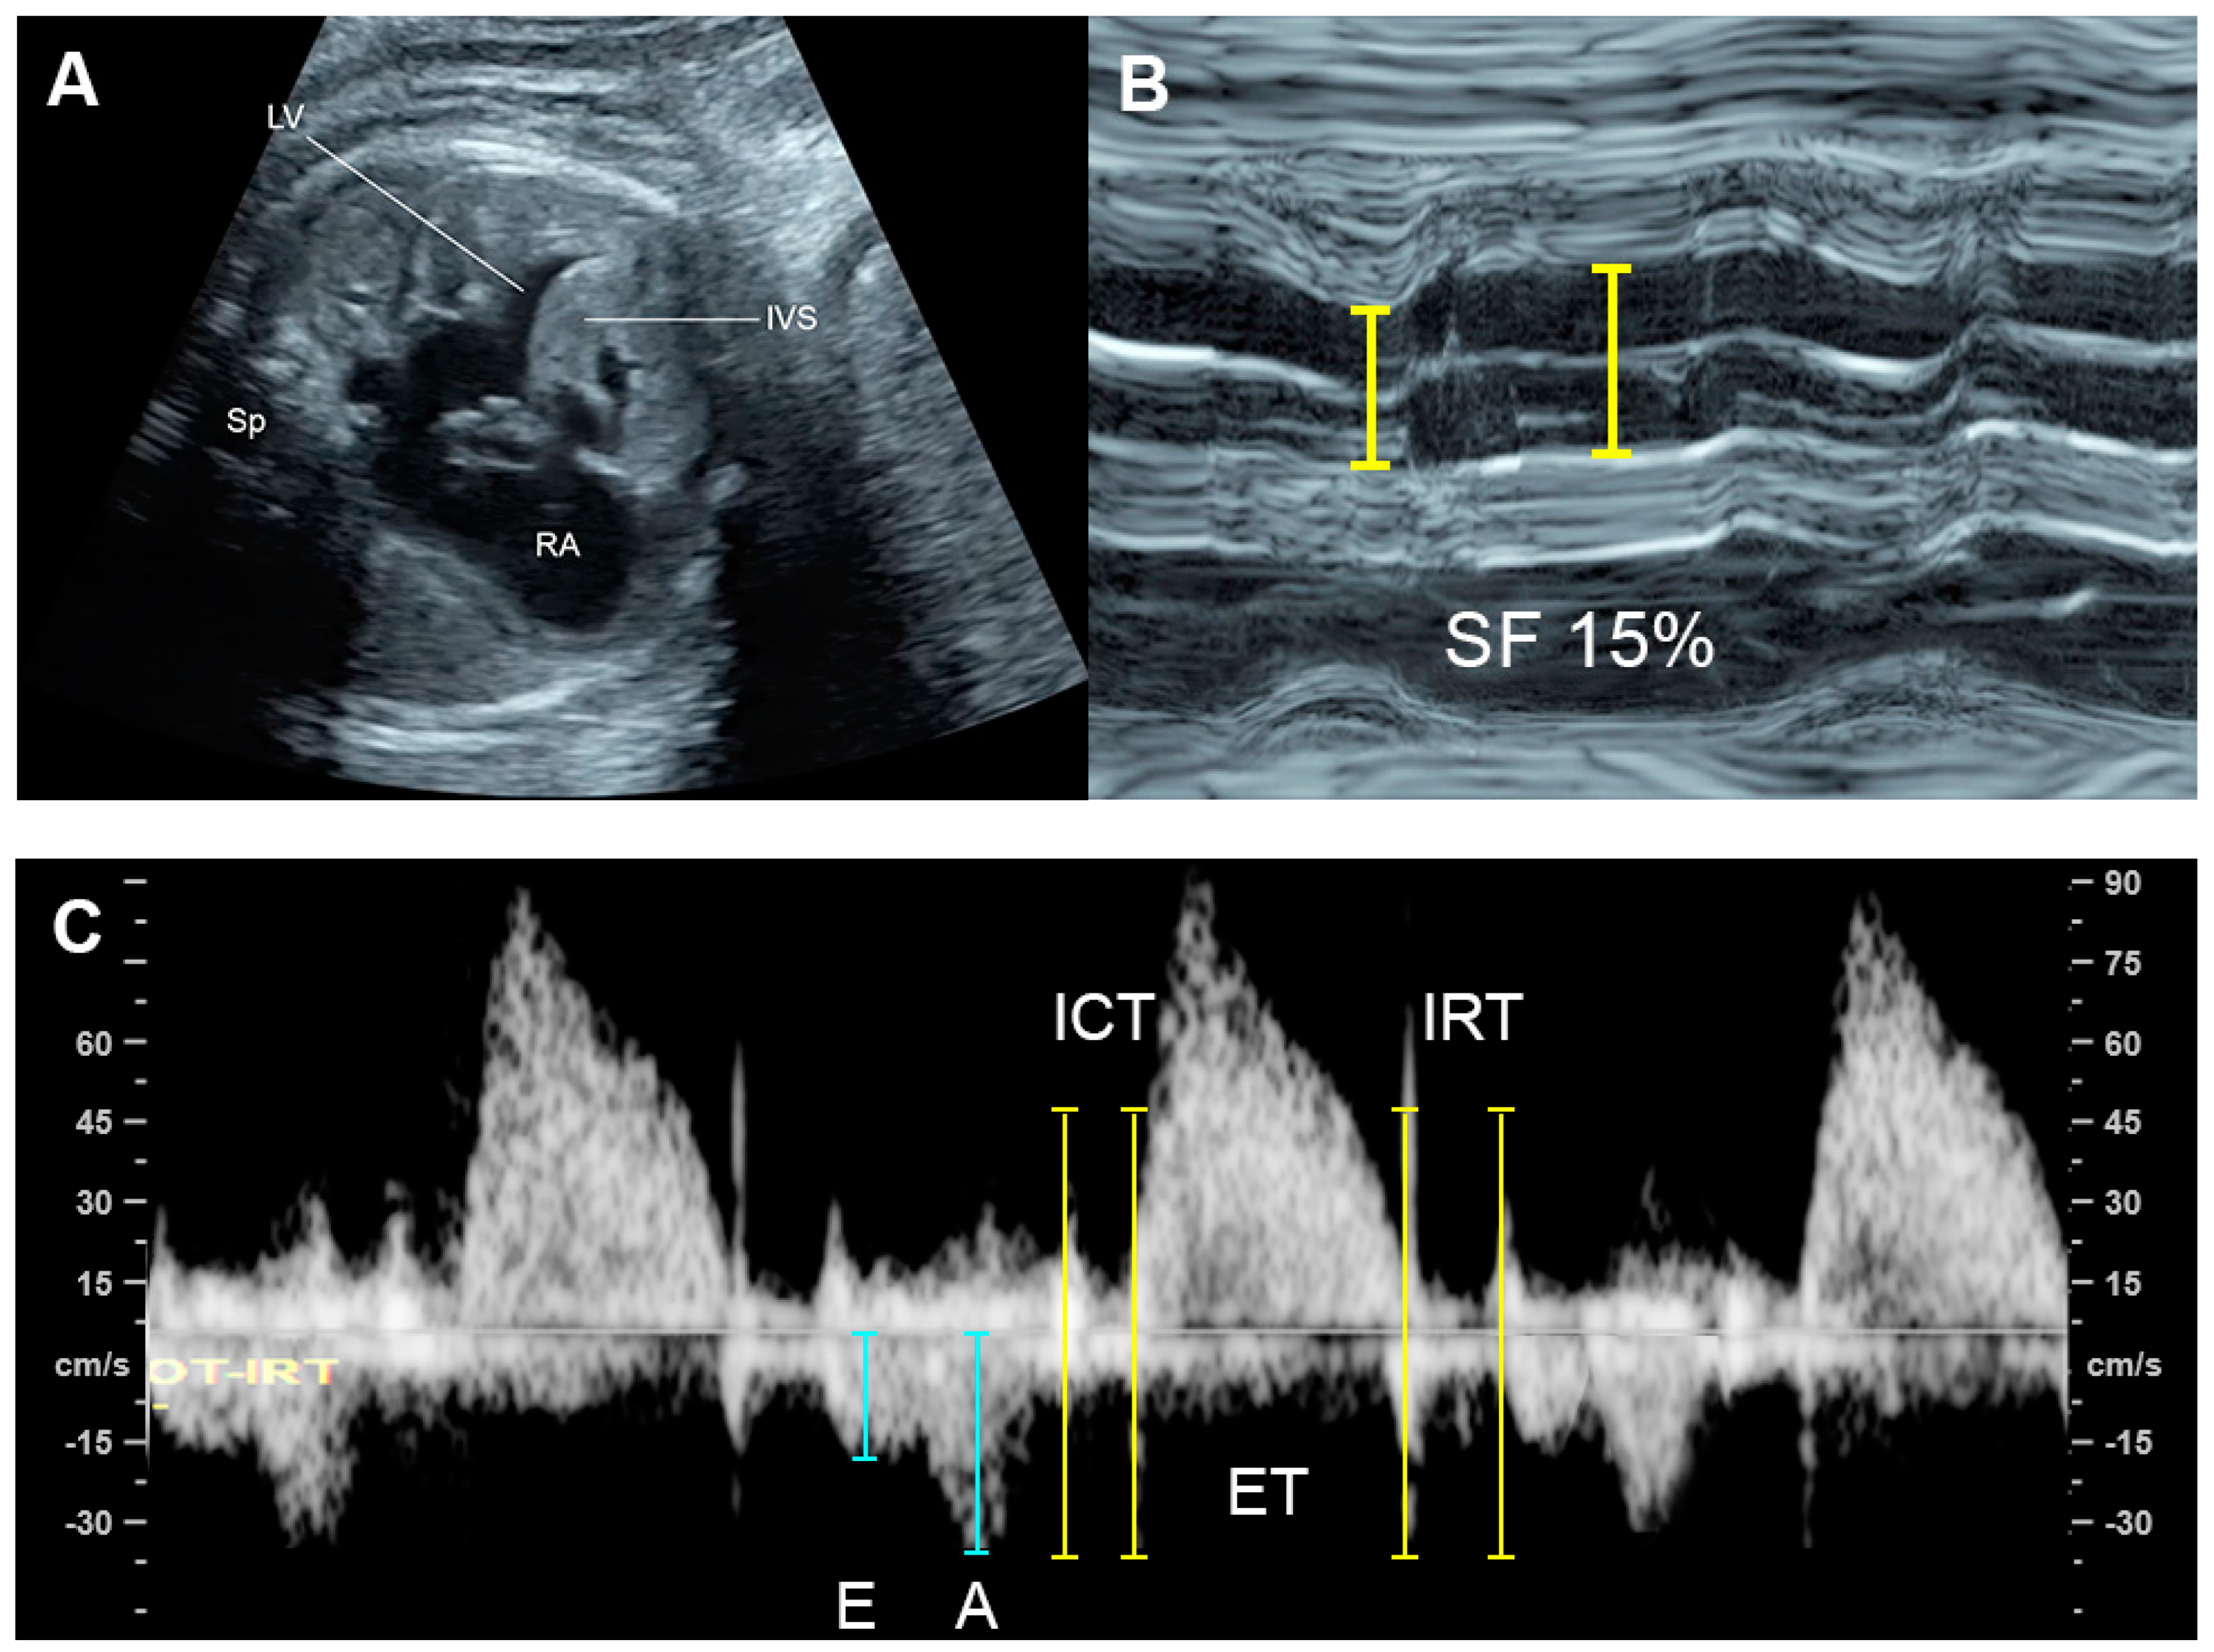

4.1. Ventricular Shortening Fraction (SF)

4.5. The Myocardial Performance Index (MPI)

| Shortening fraction | Decreased (<28%) | Systolic dysfunction |

| Tei index | Increased > 0.50 | Global cardiac dysfunction |

| ICT: 28 (22–33) ms | Prolonged | Systolic dysfunction |

| IRT: 34 (26-41) ms | Prolonged | Diastolic dysfunction |